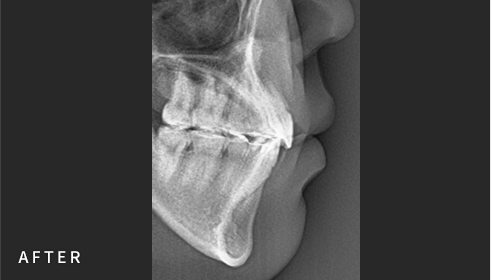

• Cephalometric X-ray 촬영

2~3초의 짧은 시간 안에

얼굴의 측면 엑스레이 촬영이 가능합니다.